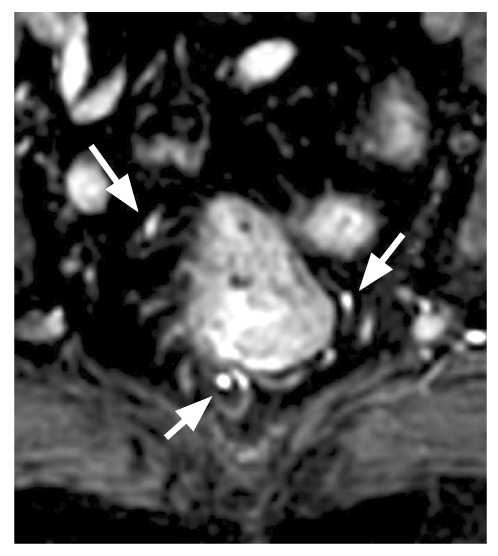

In 34% of cases, two branches of the upper rectal artery were identified, leading to trifurcation. The posterior branches branched off in the form of arcs to the posterior wall of the intestine at 5 and 7 o’clock of the conventional dial (variant 2). Figure 6 displays the first and second variants. In two observations, a vascular arcade in the form of an arc was found, which fed almost the entire circumference of the intestine, according to the blood supply type of the small intestine (variant 3) (Fig. 7). In six cases, variant 4 (Fig. 8) showed the scattered type, with six separate branches from the superior rectal artery to the intestinal wall, either simultaneously or consecutively. In 4% of cases, variant 7 had four branches of the upper rectal artery, two of which split and two went separately.

Fig. 8. Six terminal branches of the superior rectal artery before the insertion into the intestinal wall.